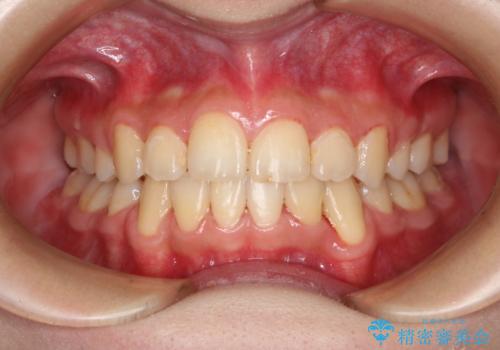

出っ歯と深い噛み合わせ:抜歯矯正で口元スッキリ!

- 出っ歯が気になるとご相談にいらした方です。抜歯して歯を並べました。深かった噛み合わせも改善させることが出来ました。

噛み合わせが元々深い方は一般的に噛む力が強く、治療に時間がかかる傾向にあります。治療前の想定よりも短期間でスムーズに治療を終える事ができ、大変喜んでいただけました。リテーナーによる保定もしっかり行っていただいており、後戻りなく快適にすごして頂けているとのことです。